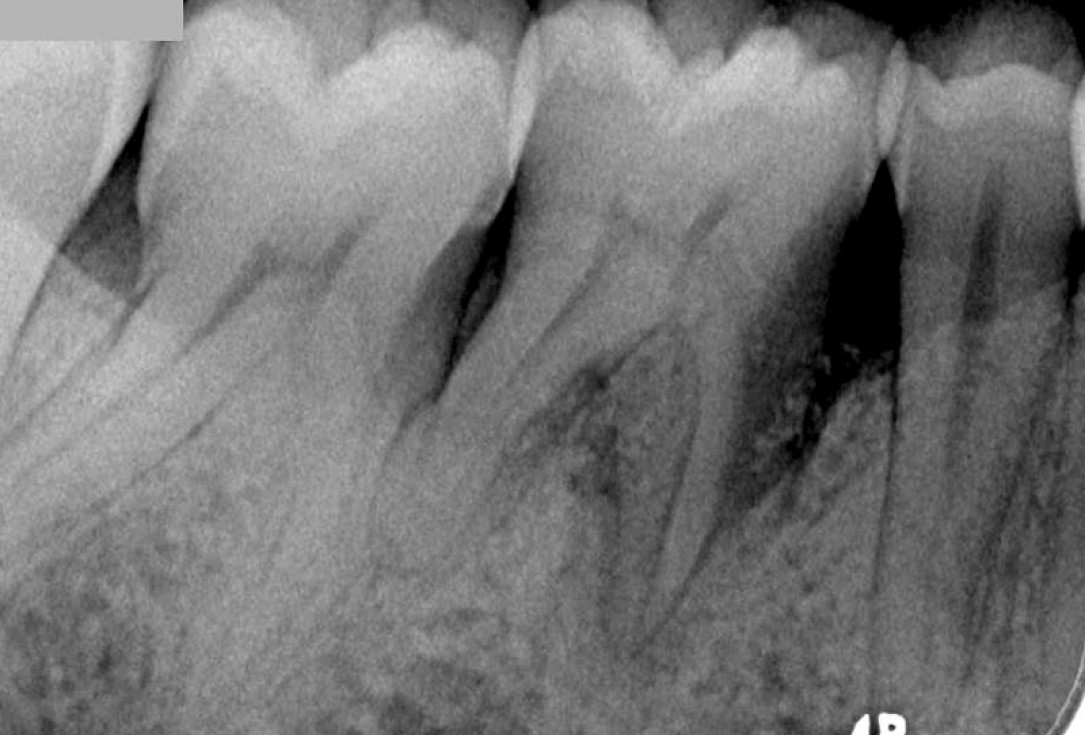

Treatment of vertical bone loss by using cerabone®, autologous bone and Jason® membrane - Prof. Rafael Ortega Lopes

The patient presented with severe pain in the lateral incisor and a deficient adhesive provisional. Bruxism resulted in canine loss and premature contact in the lateral incisor.